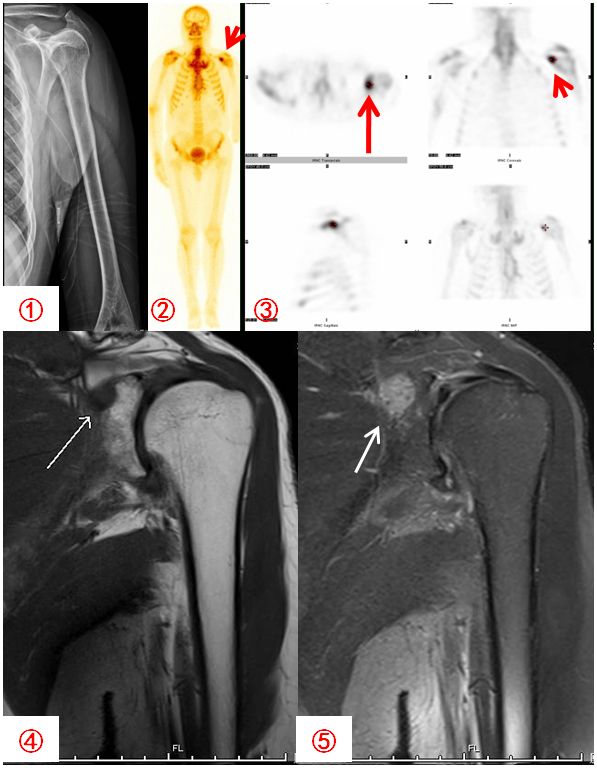

胃癌患者,自述左上臂痛,DR拍片未見明顯異常(圖1);骨顯像示左肩關(guān)節(jié)異常濃聚(圖2,紅箭),SPECT斷層顯像定位于左肩胛骨(圖3,紅箭);MR顯示病灶與ECT所示一致(圖4、5白箭)。